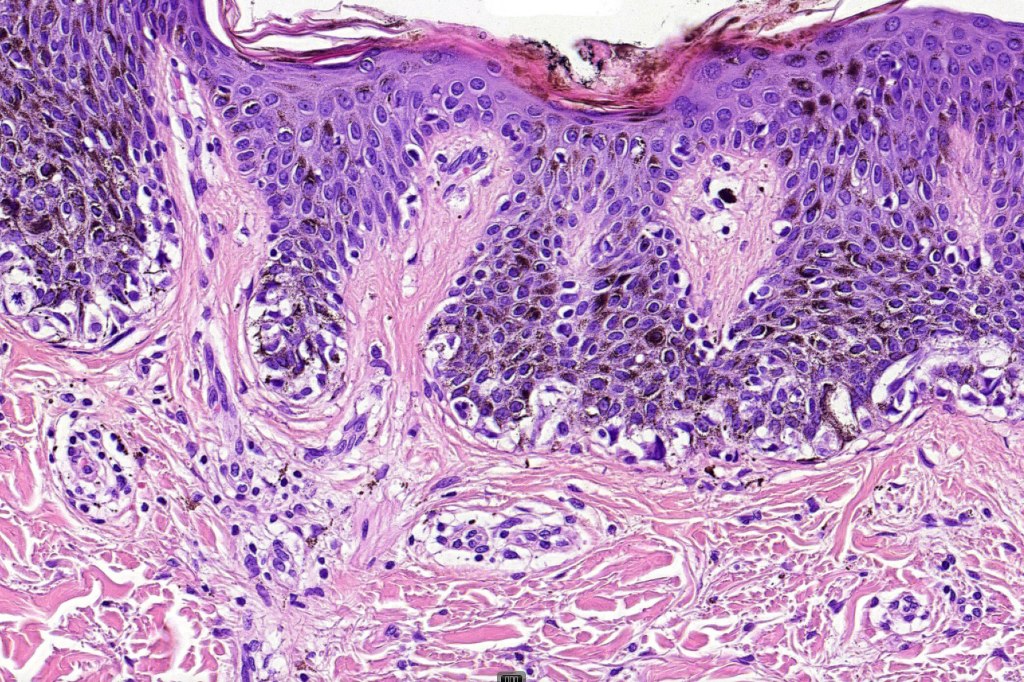

•Large dyscohesive nests with retraction artifact, not restricted to the tips of the epidermal ridges

•Heavy pigmentation (sometimes gray/green)

•Bridging common, often over multiple rete ridges

•Variable atypia (can be marked)

•Central pagetoid spread

•Junctional mitoses sometimes present, dermal mitoses+/-, can be multiple but never atypical

•Dermal fibrosis (sometimes lamellar)